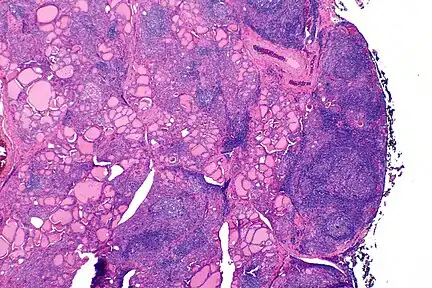

| The thyroid of someone with Hashimoto's thyroiditis as seen with a microscope at low magnification | |

Gross morphological changes within the thyroid are seen in the general enlargement, which is far more locally nodular and irregular than more diffuse patterns (such as that of hyperthyroidism). While the capsule is intact and the gland itself is still distinct from surrounding tissue, microscopic examination can provide a more revealing indication of the level of damage.[24]

Histologically, the hypersensitivity is seen as diffuse parenchymal infiltration by lymphocytes, particularly plasma B-cells, which can often be seen as secondary lymphoid follicles (germinal centers, not to be confused with the normally present colloid-filled follicles that constitute the thyroid). Atrophy of the colloid bodies is lined by Hürthle cells, cells with intensely eosinophilic, granular cytoplasm, a metaplasia from the normal cuboidal cells that constitute the lining of the thyroid follicles. Severe thyroid atrophy presents often with denser fibrotic bands of collagen that remains within the confines of the thyroid capsule.[25]